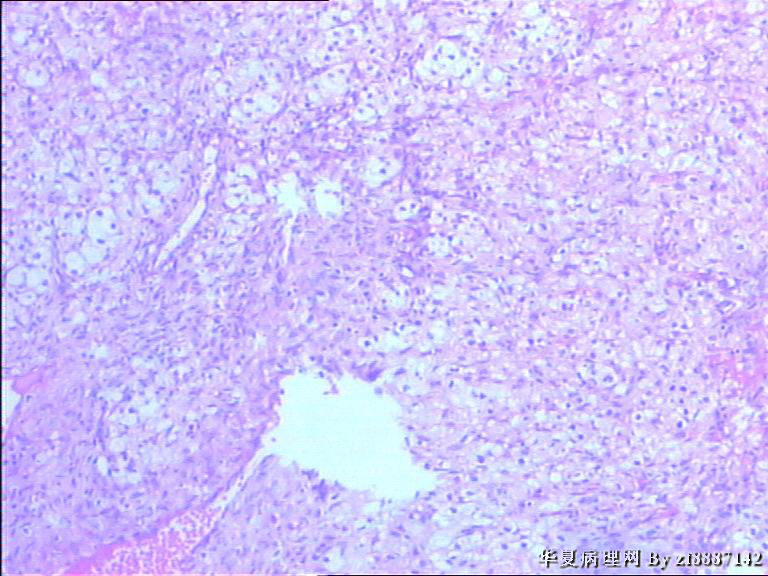

卵巢囊性肿块约3cm*3cm*3cm,表面光滑,包膜完整,内有清量液体,壁厚约0.3,

大量上看起有点向黄体,但镜下为什么胞浆这么空亮,这是什么。